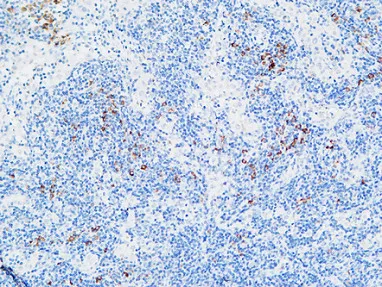

HDC Rabbit Polyclonal Antibody

Cat: APRab11956